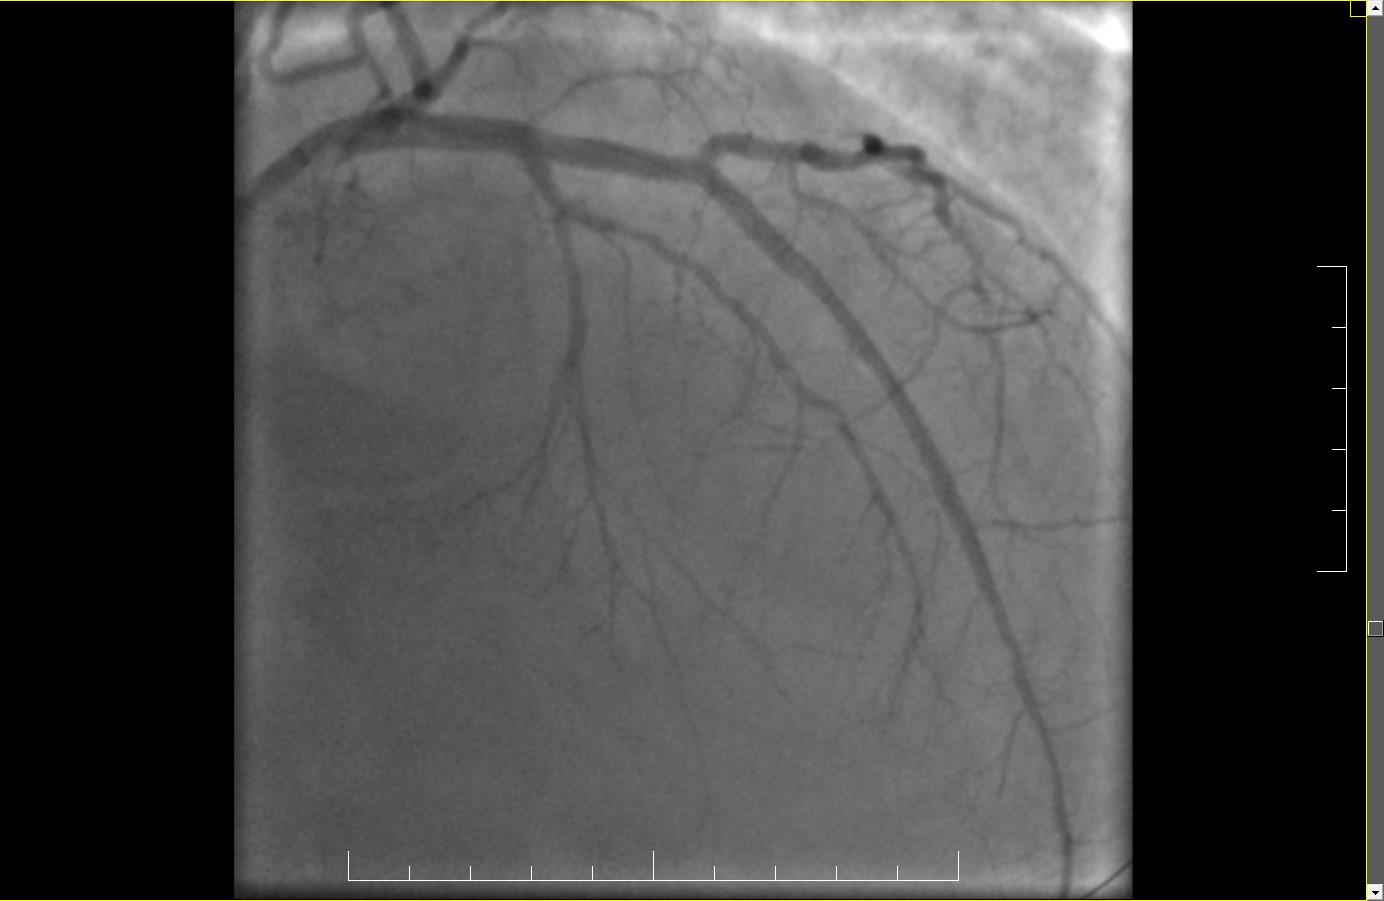

Astfel, echipa medicală formată din doctor Nicolae Cârstea, medic cardiolog interventionist și dr. Cezar Uzea, medic rezident a efectuat procedura de tratament CTO prin implantarea a două stenturi farmacologice active la nivelul vaselor îngustate.

Rezultatul procedurii este unul foarte bun, pacientul nu a mai resimțit angina pectorală și a fost externat în stare optimă. Este deosebit de important să țină cont de recomandările medicale legate de adoptarea unui stil de viață sănătos, să respecte tratamentul medicamentos prescris și să revină la controalele cardiace periodice. În imaginea de mai jos se poate observa fluxul de sânge normal din arterele inițial blocate. (Fig.2)